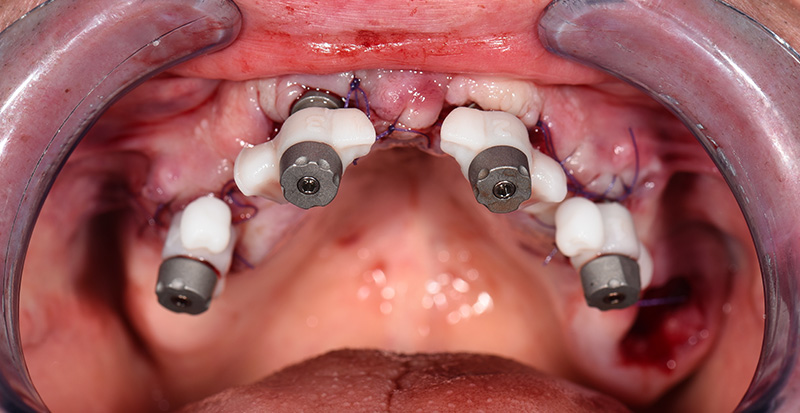

Immédiatement après la suture, des piliers de type « Scan-Transfer » de l’entreprise IPD, ont été placés sur les piliers « Multi-unit » (IPD propose des piliers « multi-unit » pour 25 marques d’implants dentaires et 80 plateformes différentes). Ceux-ci permettent une numérisation précise à l’aide d’un scanner intra-oral, selon un protocole spécifique qui évite toute distorsion de l’empreinte dans les zones édentées.

Fig. 05 : Scan-Transfers IPD en place.